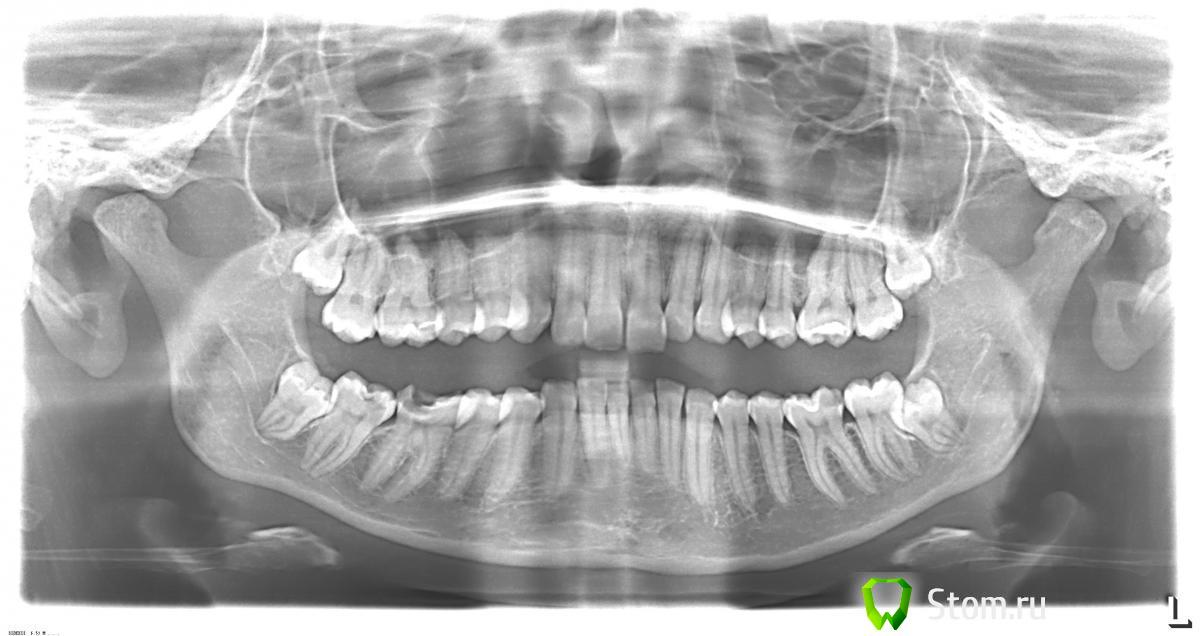

Night Опубликовано 2 марта, 2012 Поделиться Опубликовано 2 марта, 2012 Здравствуйте! посоветуйте, пожалуйста, что можно сделать в моем случае.и определиться с планом лечения. Возможно ли в моем случае лечение без хирургического вмешательства, только ортодонтией? Что вообще можно сделать без хирургического вмешательства, к какому результату можно прийти? Реально ли вообще передние зубы "поставить на место"? Очень хочется послушать мнения специалистов.http://s43.radikal.ru/i101/1203/4d/dea697e5a4f7t.jpg Ссылка на комментарий

Force Опубликовано 5 марта, 2012 Поделиться Опубликовано 5 марта, 2012 Хирургия конечно вариант выбора, но можно и без нее обойтись. Ссылка на комментарий